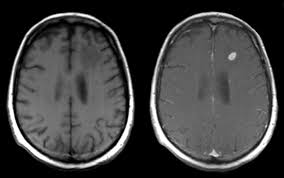

Signs Of Metastatic Breast Cancer In Brain / How Research Is Failing Women With Metastatic Breast Cancer Time : They are usually named after the tissue or organ where the cancer first developed (for example, metastatic lung or breast cancer tumors in the brain, which are the most.. Metastatic brain tumors (also termed secondary brain tumors) are made of cancerous cells that spread through the bloodstream from a tumor located elsewhere in the body. Webmd medical reference reviewed by brunilda nazario. Metastasis is most often found when people report symptoms, such as bone pain, to. Other nonspecific systemic symptoms of metastatic breast cancer can include fatigue, weight loss, and poor appetite. The incidence of brain metastasis from breast cancer (24 % in this review) is increasing due to advances in both imaging technologies leading to earlier detection of the brain metastases and introduction of novel therapies resulting in longer survival from the primary breast cancer.

Metastatic breast cancer means the cancer has spread from your breast to distant organs such as your bones, lungs, or other parts of your body. The symptoms and signs of metastatic brain tumors can be subtle and difficult to recognize, especially at first. Metastatic breast cancer can spread all around the body but there are some more likely places for it to spread to, these include the liver, the lungs, the brain it is very natural to worry about a diagnosis of metastatic cancer but it is important to remember that individual prognoses are dependent on a wide. Metastases from breast cancer can be a frequent finding in routine oncoradiological practice. Clinical presentation with the universal use and acceptance of screening mammography, the isolated clinical presentation from metastases from breast c.

An overview of the presentation, diagnosis. Webmd medical reference reviewed by brunilda nazario. Sometimes people with metastatic breast cancer do not have any of these changes. Metastatic cancer can display general symptoms and symptoms at specific sites of metastasis. Metastatic breast cancer, also referred to as metastases, advanced breast cancer, secondary tumors, secondaries or stage iv breast cancer, is a stage of breast cancer where the breast cancer cells have spread to distant sites beyond the axillary lymph. Signs and symptoms of metastasis. Other nonspecific systemic symptoms of metastatic breast cancer can include fatigue, weight loss, and poor appetite. Metastatic cancer that spreads from its original location is known by the name of the primary cancer. After lung cancer, metastatic breast cancer is the second most common cancer associated with brain metastases in the united states 1. Signs of cancer in the brain include headaches, seizures, vision changes, and dizziness. Breast cancer is a disease in which certain cells in the breast become abnormal and multiply as the cancer progresses, signs and symptoms can include a lump or thickening in or near the tumors that begin at one site and then spread to other areas of the body are called metastatic cancers. They are usually named after the tissue or organ where the cancer first developed (for example, metastatic lung or breast cancer tumors in the brain, which are the most. The cancer has spread to other parts of the body.

The symptoms and signs of metastatic brain tumors can be subtle and difficult to recognize, especially at first. The cancer has spread to other parts of the body. This usually includes the lungs, liver, bones or brain. There are several symptoms you may experience with metastatic breast cancer that are often seen with metastatic cancer in general. After lung cancer, metastatic breast cancer is the second most common cancer associated with brain metastases in the united states 1.